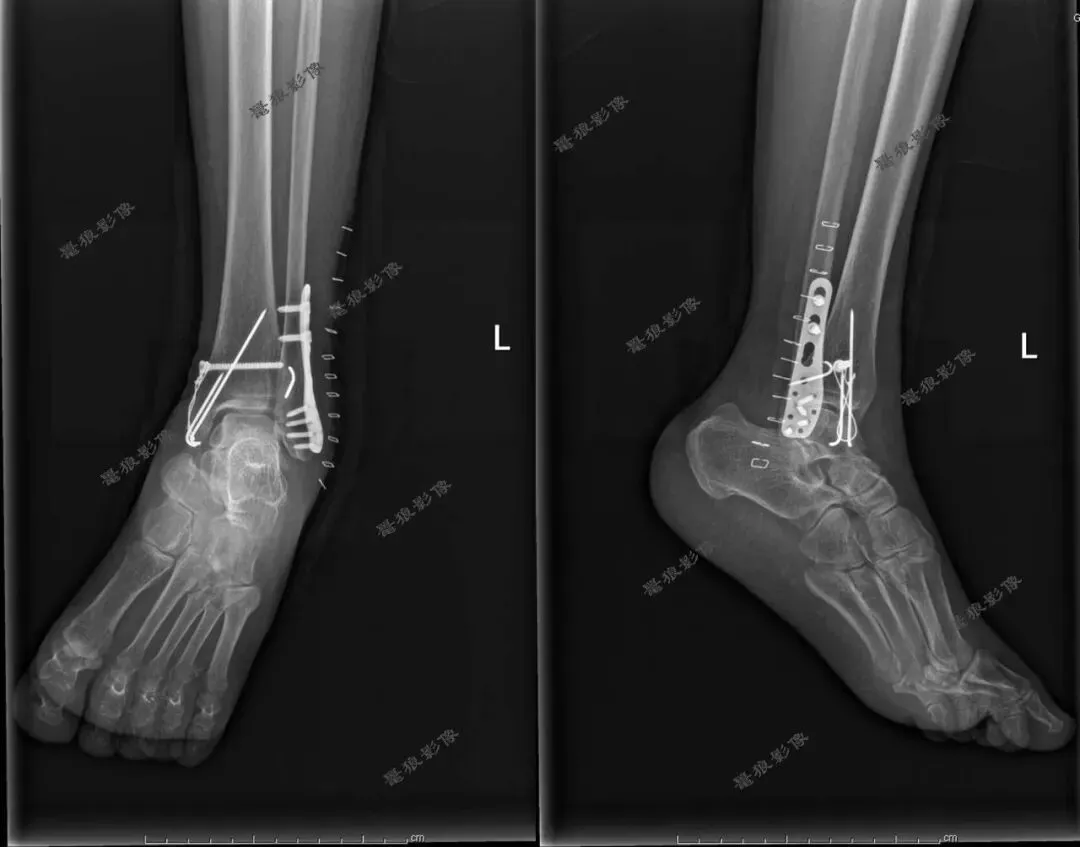

F,62y。跌伤左踝部肿痛活动受限3小时余。

术前CT:

1、左三踝粉碎性骨折,胫距关节半脱位,踝关节软组织肿胀;

2、左足舟状骨、内侧楔骨、第1-4跖骨近端骨折。

术后X线:

1、左三踝骨折内固定术后;

2、考虑左足第3、4跖骨基底部骨折可能;

请结合临床及术前CT。